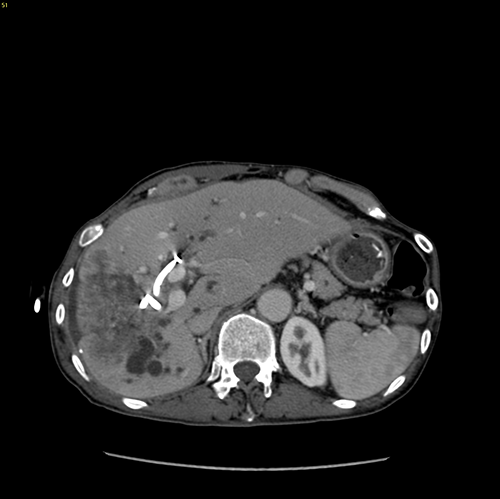

右肝胆管细胞癌、胆道梗阻---右三肝切除、左肝管空肠Roux-en-Y切除